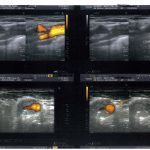

stenose-carotide-interne-droite